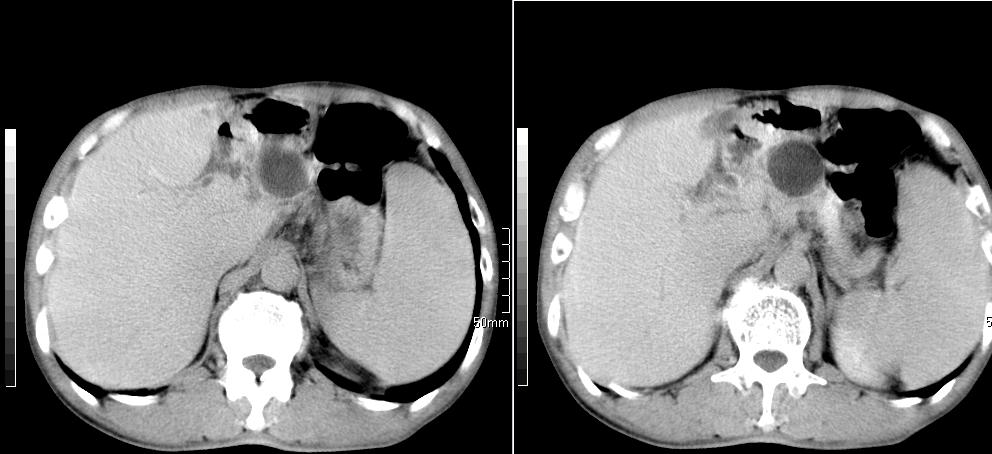

标题: CT26769:男,58岁,腹胀、腹部不适一年余 [打印本页]

标题: CT26769:男,58岁,腹胀、腹部不适一年余

1 慢性胰腺炎并假囊肿形成。2 慢性胆囊炎并累及肝边缘!

1)考虑慢性胰腺炎并假性囊肿形成。2) 慢性胆囊炎。3)肝内胆管扩张。

1肝内胆管扩张,性质待定,2慢性胰腺炎胰管扩张,胰腺颈部假囊肿,3肝左叶低密度为小囊肿,4胆囊炎。